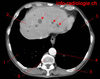

Le patient a une diverticulite. Devant persitance fièvre et augmentation du sd inflammatoire à 48h on réalise le TDM suivant. Vu la taille de l’abcès (>5 cm on va dire), quelle CAT?

drainage de l’abcès: ponction percutanée écho ou scanno-guidée; OU drainage chirurgical si percut impossible (avec RDC à distance)